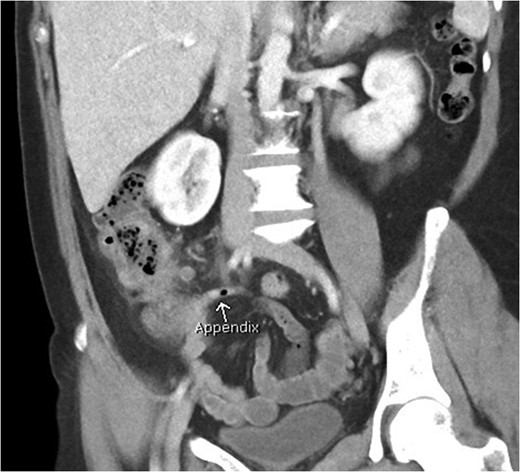

Coronal view of patient with caecal carcinoma. Normal (non-dilated) appendix (arrow).

There are a number of CT features that help distinguish bowel wall thickening from malignant and benign causes [3]. A neoplastic cause is suggested if there is focal bowel wall thickening (less than 5 cm of extension) which is typically asymmetrical and eccentric. These may have homogeneous contrast enhancement due to infiltration of a tumour mass, or a heterogeneous areas of low attenuation from ischaemia and necrosis, findings with a sensitivity of up to 97% [4]. Malignancy may also have shouldered edges as opposed to tapering transition to normal bowel wall. Appendiceal dilatation, if present, may be thin walled and without inflammatory stranding due to a gradual obstructive process, although appendicitis can be a presenting symptom for carcinoma. Regional lymphadenopathy and distal metastases, when present, support the diagnosis.